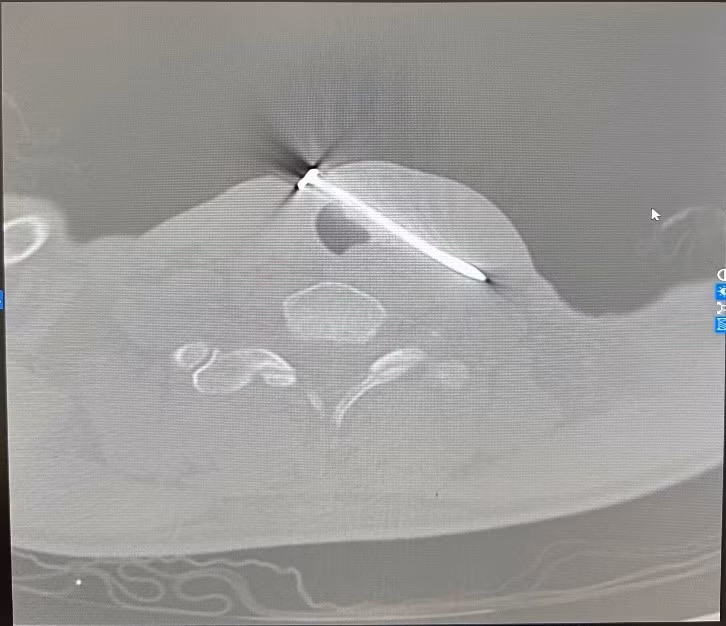

Kết quả cho thấy dị vật xuyên qua thành bên trái khí quản và đường đi của tĩnh mạch cảnh trong trái, một tổn thương cực kỳ nguy hiểm, có nguy cơ gây suy hô hấp cấp, sốc mất máu và tử vong nếu không được can thiệp kịp thời.

Hình ảnh đinh sắt trên phim chụp - Ảnh BVCC